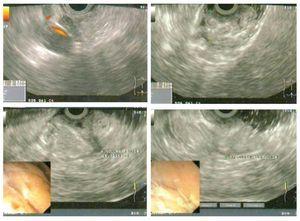

Mujer de 41 años, que se presentó a consulta con un gastroenterólogo por dolor abdominal alto, de tres meses de evolución, inespecífico, sin factores que lo atenuaran o exacerbaran. Fue evaluada mediante endoscopia con la que se evidenció tumoración gástrica submucosa (Figura 1). La biopsia superficial reveló gastritis moderada. La paciente fue referida a ultrasonido endoscópico que confirmó masa submucosa con zonas quísticas consistentes con necrosis de 4 cm por 4 cm (Figura 2). Se estableció el diagnóstico endoscópico de probable tumor del estroma gastrointestinal y la paciente se envió a cirugía. Se le realizó una resección distal gástrica en cuña y el análisis histopatológico reveló duplicación gástrica congénita de 4 cm. La paciente se recuperó sin complicaciones.

¿ Figura 2. Imagen de ultrasonido endoscópico.